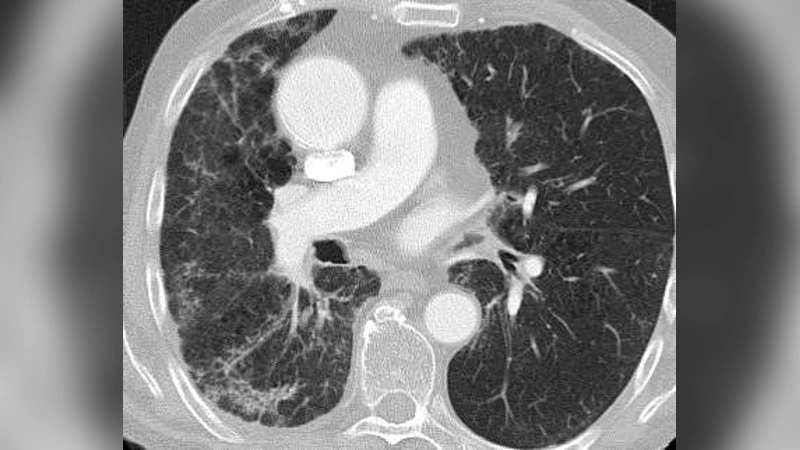

Topological texture features were compared in their ability to classify morphological patterns known as ‘honeycombing’ that are considered indicative for the presence of fibrotic interstitial lung diseases in high-resolution computed tomography (HRCT) images. For 14 patients with known occurrence of honey-combing, a stack of 70 axial, lung kernel reconstructed images were acquired from HRCT chest exams. A set of 241 regions of interest of both healthy and pathological (89) lung tissue were identified by an experienced radiologist. Texture features were extracted using six properties calculated from gray-level co-occurrence matrices (GLCM), Minkowski Dimensions (MDs), and three Minkowski Functionals (MFs, e.g. MF.euler). A k-nearest-neighbor (k-NN) classifier and a Multilayer Radial Basis Functions Network (RBFN) were optimized in a 10-fold cross-validation for each texture vector, and the classification accuracy was calculated on independent test sets as a quantitative measure of automated tissue characterization. A Wilcoxon signed-rank test was used to compare two accuracy distributions and the significance thresholds were adjusted for multiple comparisons by the Bonferroni correction. The best classification results were obtained by the MF features, which performed significantly better than all the standard GLCM and MD features (p < 0.005) for both classifiers. The highest accuracy was found for MF.euler (97.5%, 96.6%; for the k-NN and RBFN classifier, respectively). The best standard texture features were the GLCM features ‘homogeneity’ (91.8%, 87.2%) and ‘absolute value’ (90.2%, 88.5%). The results indicate that advanced topological texture features can provide superior classification performance in computer-assisted diagnosis of interstitial lung diseases when compared to standard texture analysis methods.

Fourteen patients with confirmed honeycombing on HRCT were retrospectively selected. From each examination, a stack of 70 axial, lung‑kernel reconstructed slices was obtained. An experienced thoracic radiologist delineated 241 regions of interest (ROIs): 152 from apparently healthy lung parenchyma and 89 from pathological honeycombing zones. Each ROI measured 32 × 32 pixels and was intensity‑normalized prior to feature extraction.

3. Minkowski Functionals (MF) – Three topological measures (area, perimeter, Euler characteristic χ) calculated after binarizing each ROI at eight equally spaced thresholds. The Euler characteristic, χ, captures the number of connected components minus the number of holes, thereby encoding the intricate network‑like architecture of honeycombing.